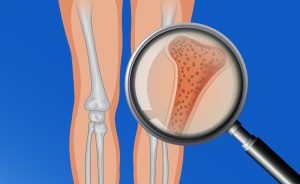

Cuando nos referimos a esta patología, estamos haciendo referencia a una neuropatía, es decir, un daño en el nervio. En este caso, el nervio al que hacemos referencia es el nervio interdigital del pie. Por lo tanto, las personas que sufren neuroma de Morton, van a referir un dolor en el pie. Esta patología se produce por una compresión del nervio interdigital generalmente entre el tercer y cuarto metatarsiano, aunque también lo podemos encontrar el dolor entre el segundo y el tercer metatarsiano.

Esta comprensión nerviosa produce una irritación en el nervio a su paso por la parte distal del metatarsiano cuando el nervio de introduce al final de su recorrido por un pequeño túnel, donde se produce el atraimiento del nervio.

El dolor que produce esta patología es un dolor muy bien localizado entre el tercer y cuatro dedo por norma general o también entre el segundo y tercer dedo, a ala altura de la flexión de los dedos de los pies. Es un dolor de tipo quemazón o eléctrico, que cursa de manera inconstante. Se suele activar el dolor al realizar una compresión de la parte delantera del pie, apoyar el peso del cuerpo también en la parte delantera, o al utilizar un calzado con mucho tacón y la parte delantera de la horma muy estrecha.